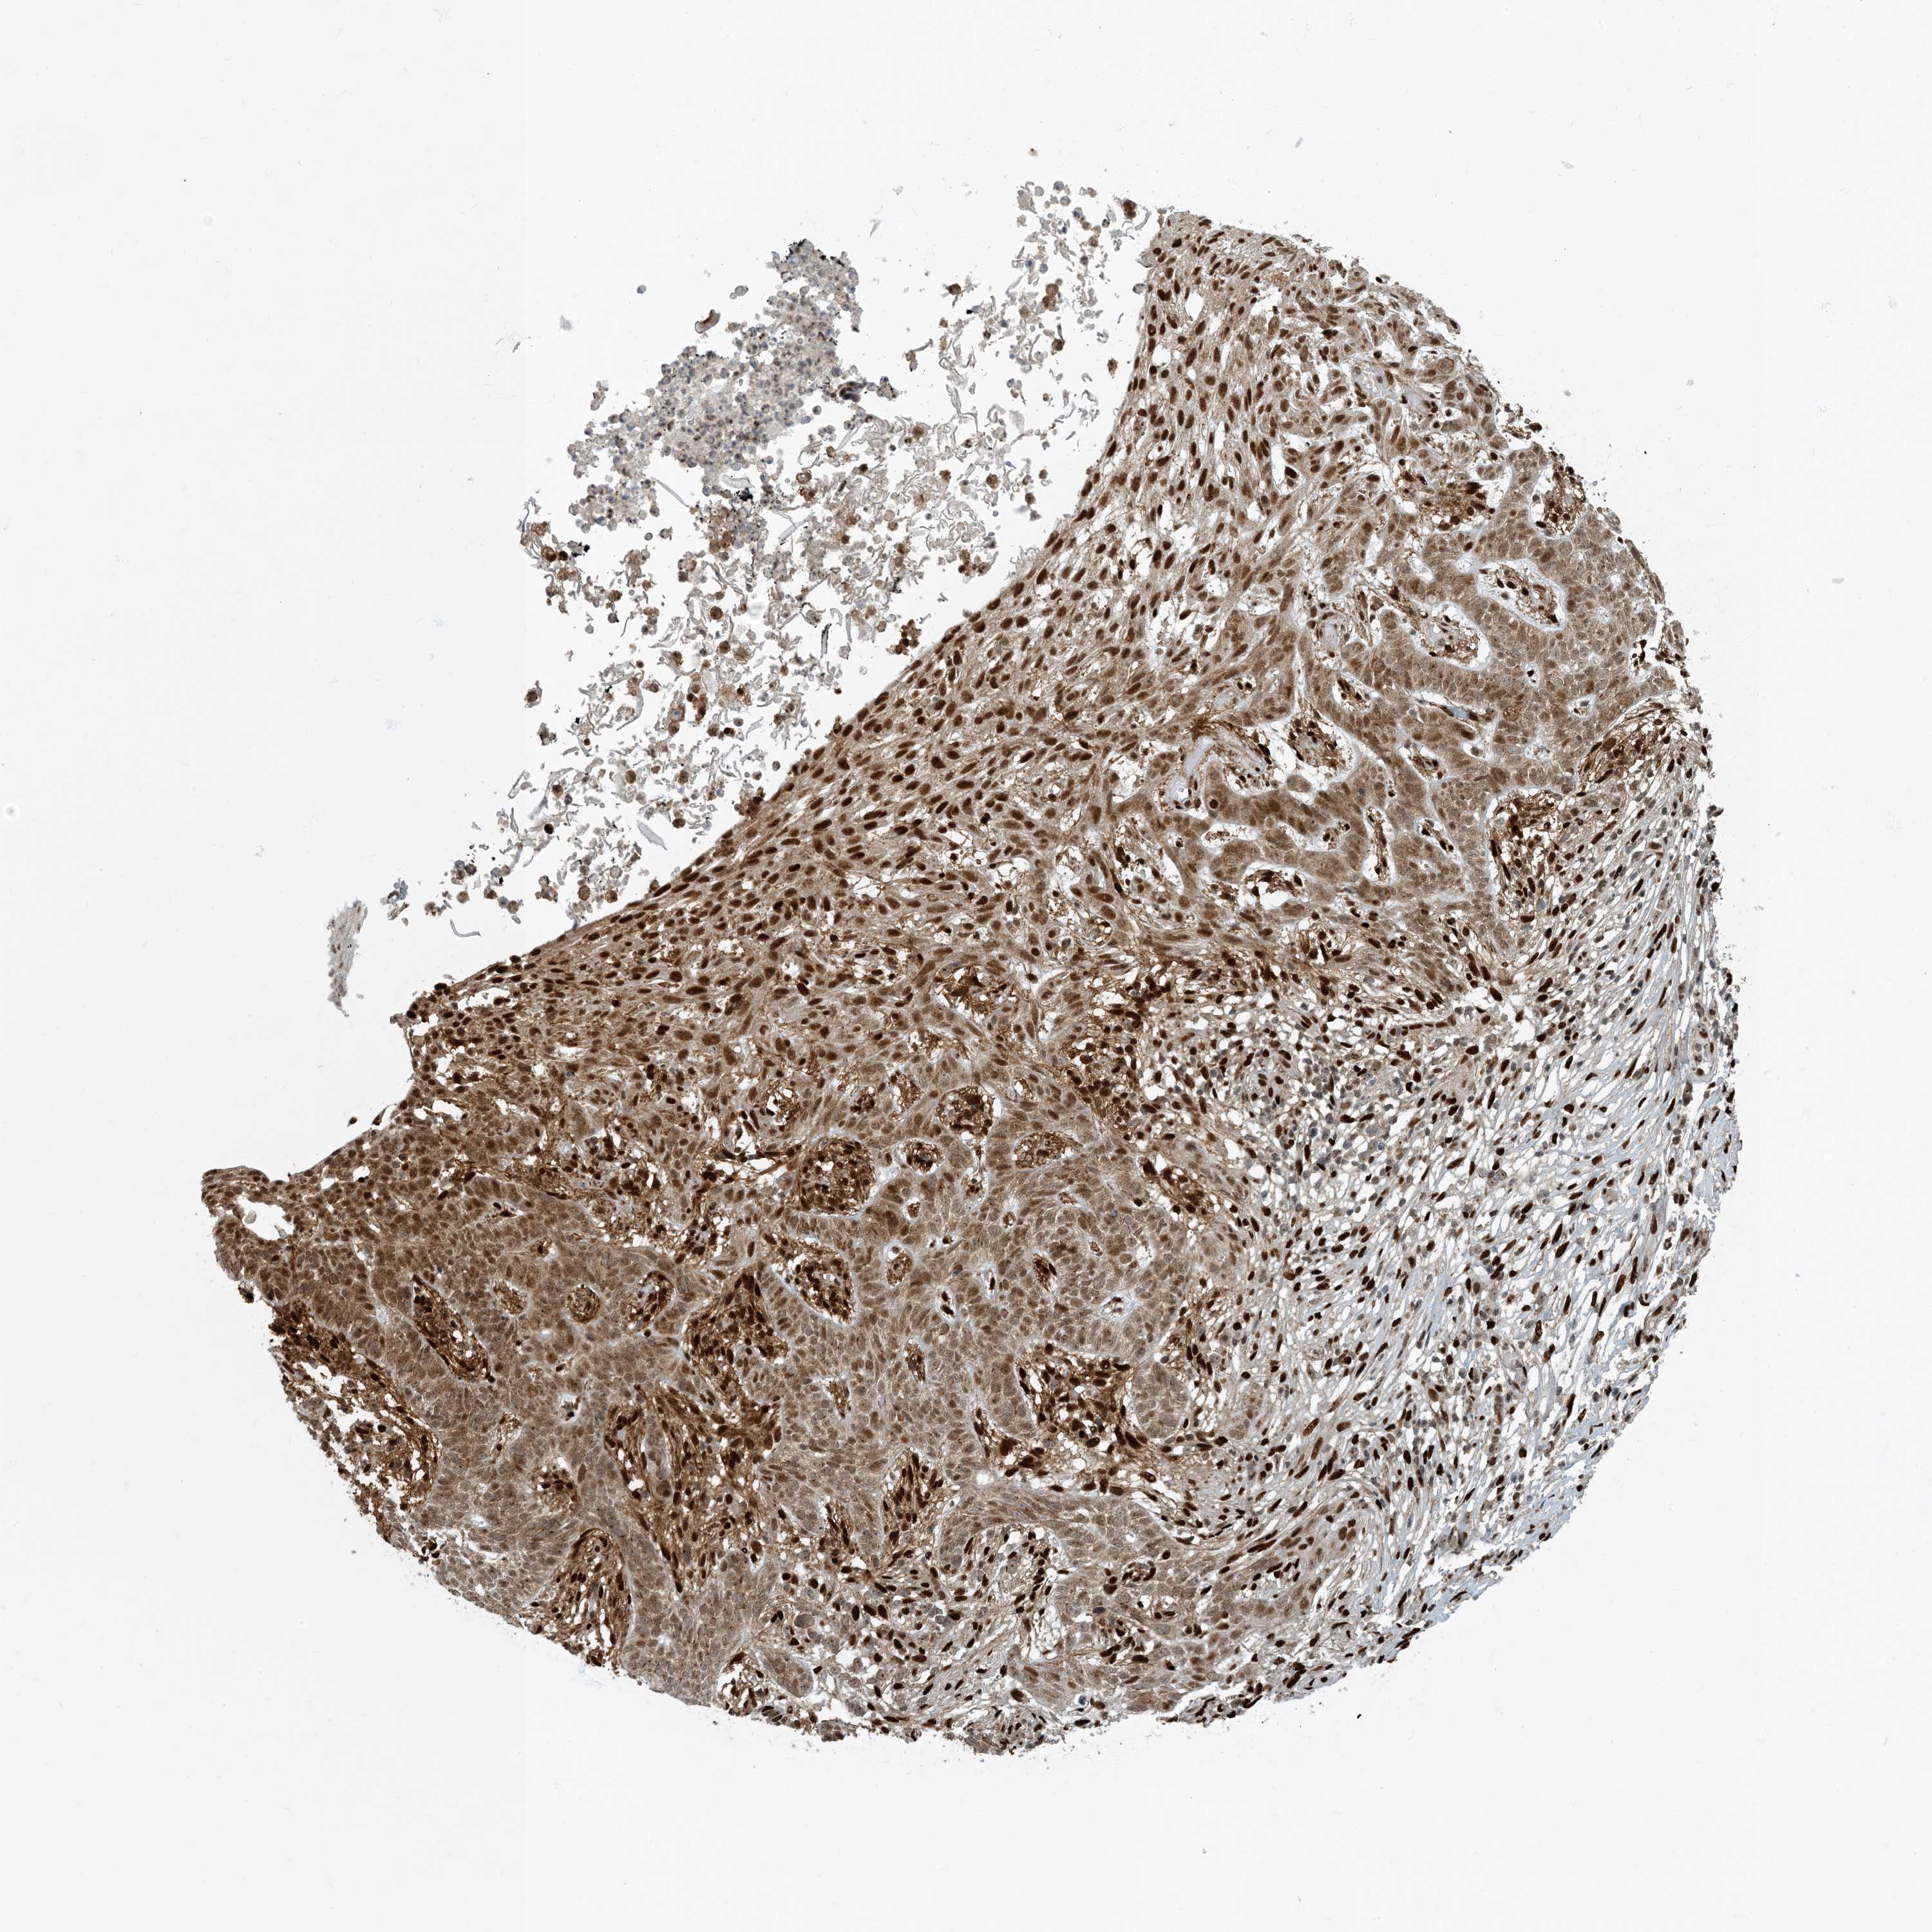

SKIN CANCER - Protein expressioni

A mouse-over function shows sample information and annotation data. Click on an image to view it in a full screen mode. Samples can be filtered based on level of antibody staining by selecting one or several of the following categories: high, medium, low and not detected. The assay and annotation is described here.

Each image is clickable and will lead to virtual microscopy that enables deeper exploration of all samples and also displays staining intensity scores, fraction scores and subcellular localization as well as patient and tissue information for each sample.

Antibody CAB009017

Staining

High

Intensity

Strong

Quantity

>75%

Location

Nuclear

Squamous cell carcinoma in situ, NOS

Squamous cell carcinoma, NOS